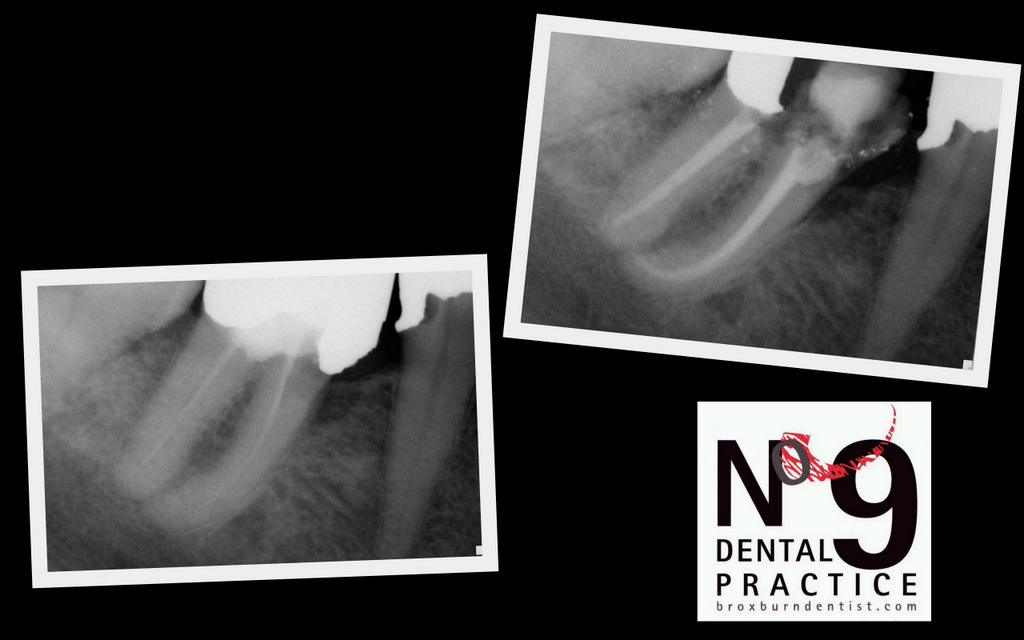

This is today's completed pain free root canal.

The before picture, on the left, shows a poorly filled root canal system. The picture on the right is the completed properly filled root canal system. All we have to do now is re-build the tooth. Many people worry about root canal. At No9 root canal is a routine pain free procedure that means you can keep your teeth for longer. We use the latest tools and techniques, this makes the procedure really very predictable. Another tooth saved from the bin at No9.